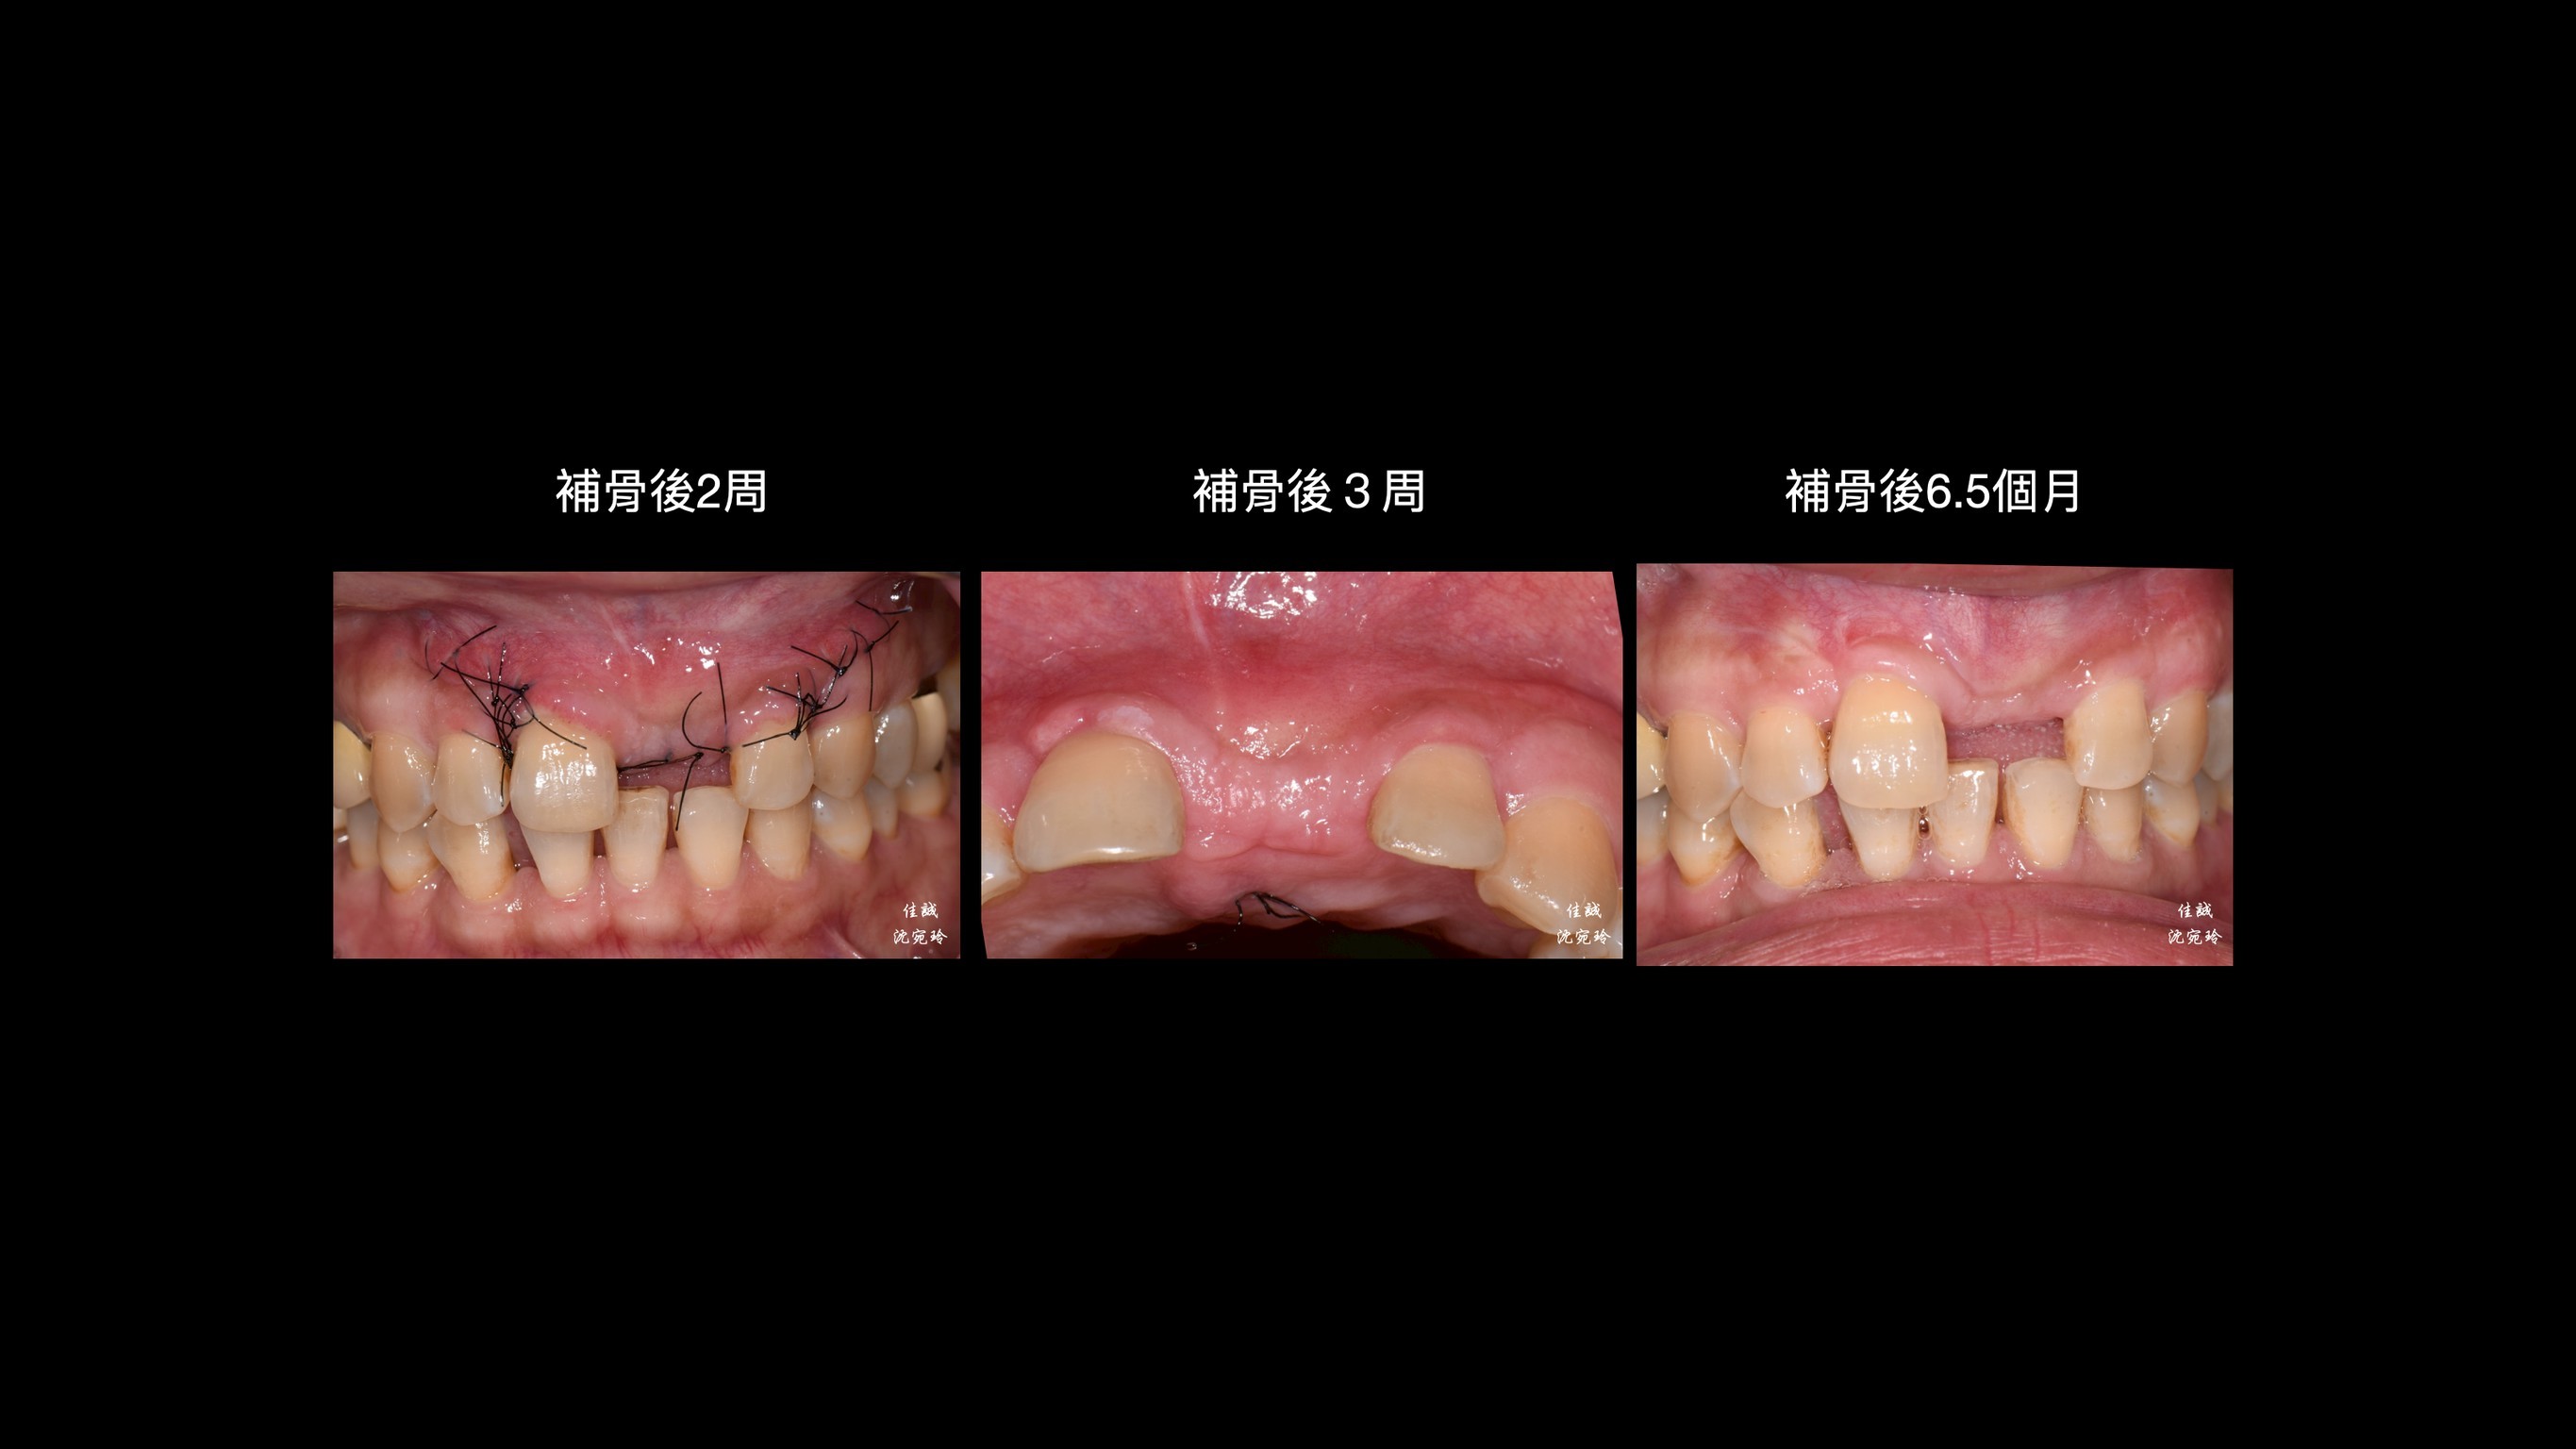

C小姐經其他醫師轉診,因上顎門牙牙根斷裂,感染而造成膿腫,在頰側、顎側、垂直高度皆有嚴重骨缺損。因此在補骨手術中,醫師選擇使用高難度的鈦網合併適度皮瓣減張,可以有效率的達到接近理想的成果。